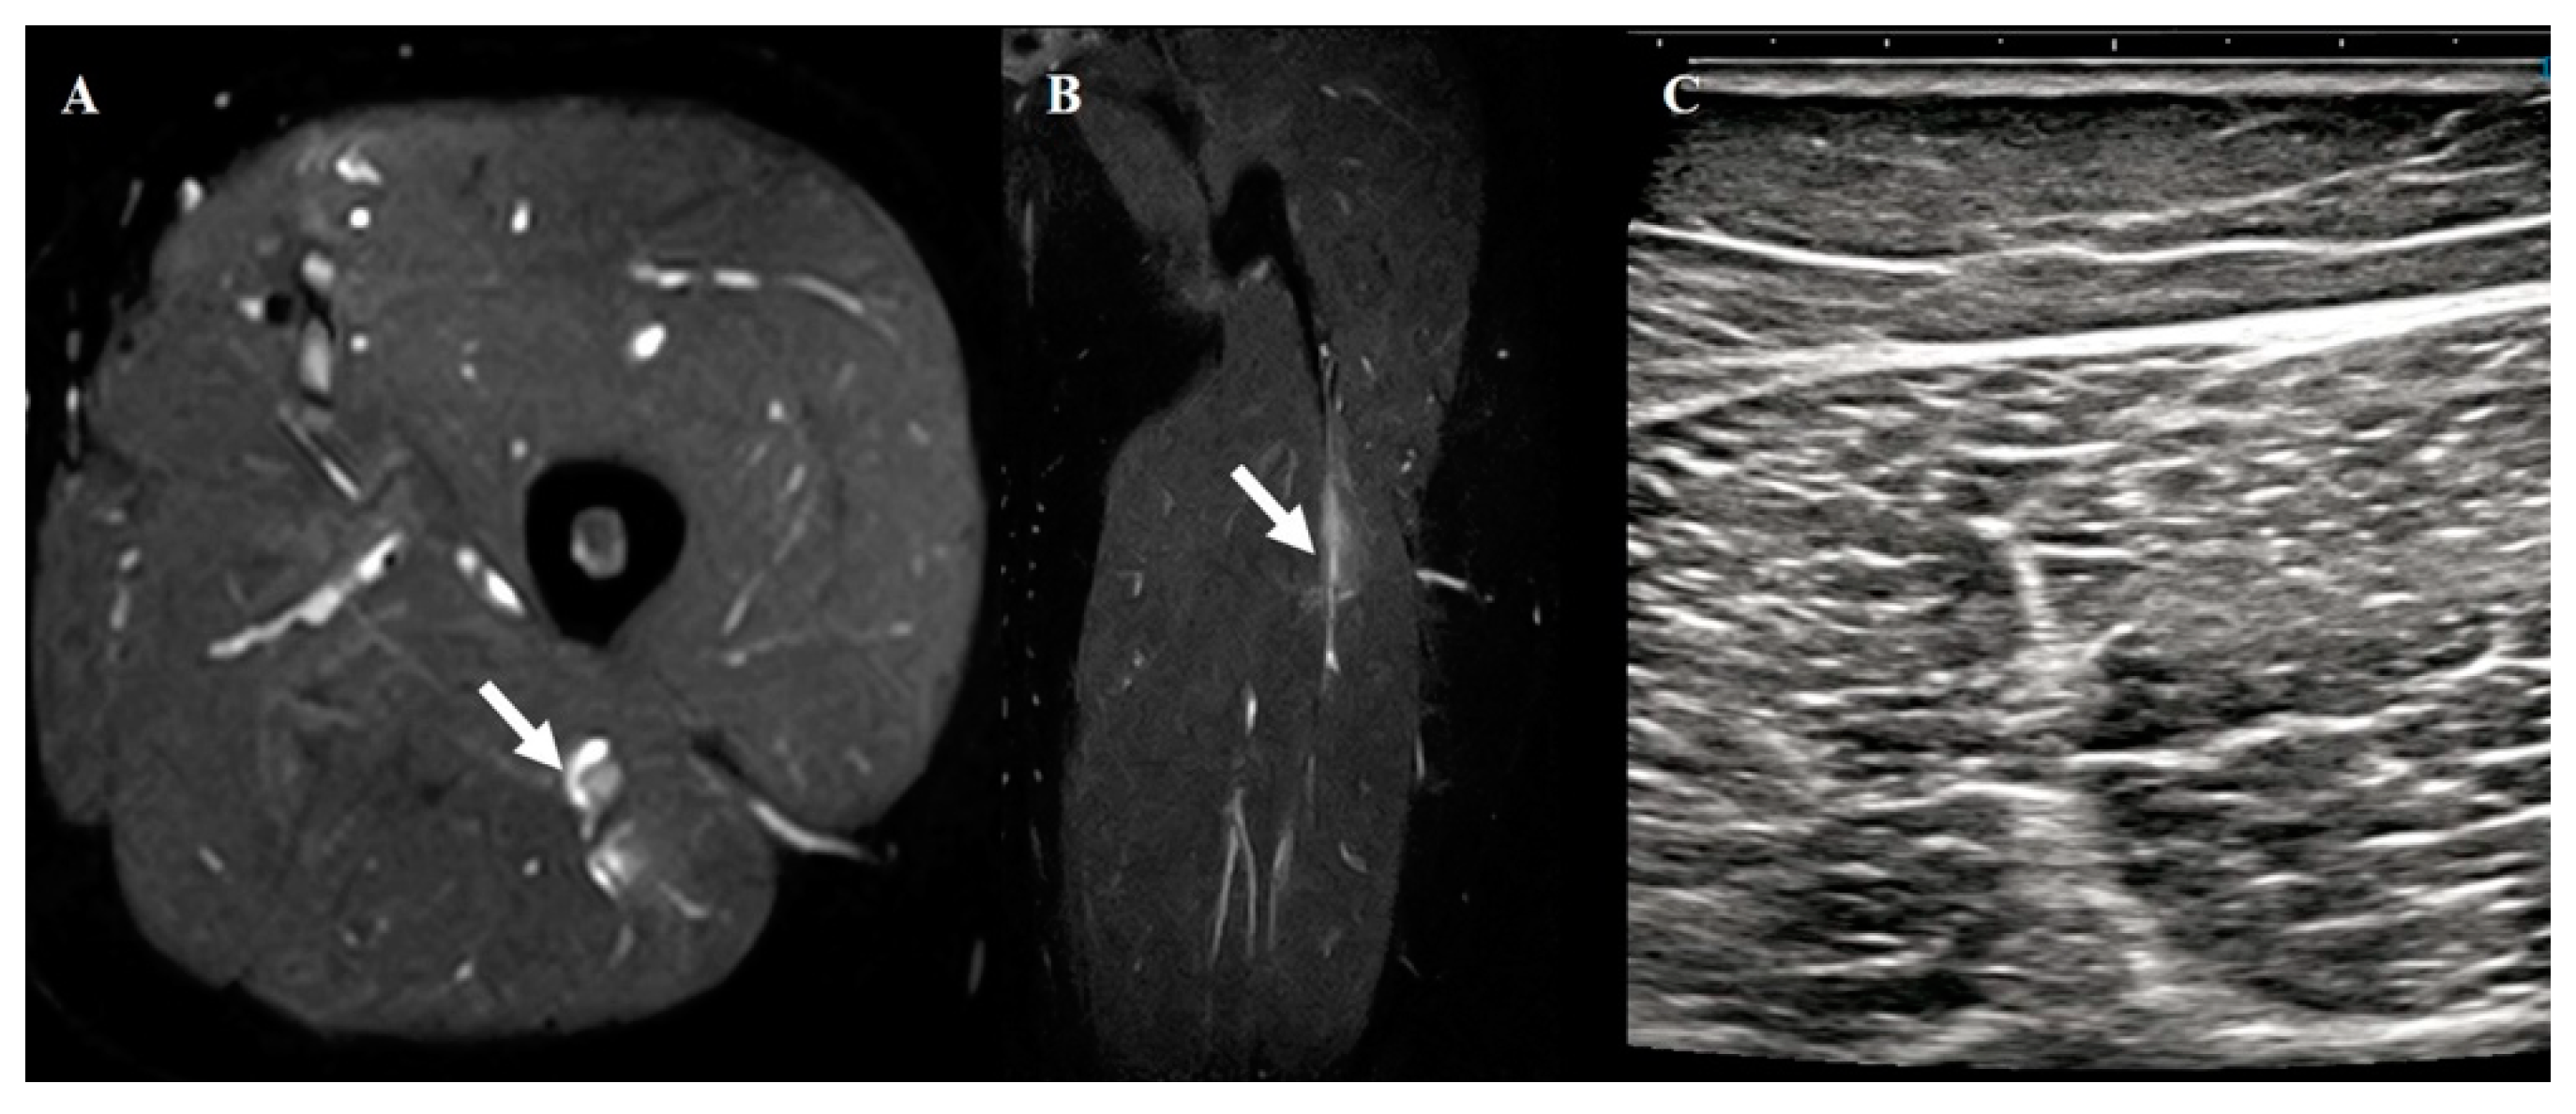

2.3. Hamstring Muscle Diagnosis Using US

- Changes in echogenicity or fiber disruption within the muscle.

- Edema or hemorrhage, defined as areas of increased echogenicity with or without visible fiber disruption in orthogonal planes.

- Hypoechoic fluid tracking along the fascial layer surrounding the muscle was indicative of intermuscular hematoma.

2.4. Hamstring Muscle Diagnosis Using MRI